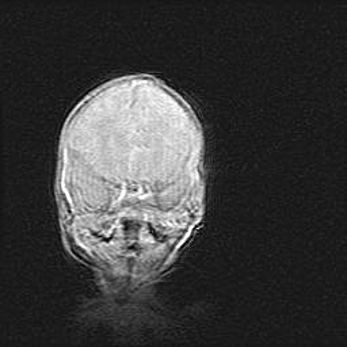

Наружная гидроцефалия с возможной атрофией височных областей.

Возраст: 28 дней

Вес: 3670 г

Пол: мужской

Окружность головы: 38 см

Срок гестации: 40 недель

Гидроцефалия головного мозга у новорожденных – это заболевание, которое характеризуется скоплением избыточного количества спинномозговой жидкости в желудочковой системе головного мозга в результате затруднения её перемещения от места выработки к месту поглощения в кровеносную систему или вследствие нарушения абсорбции. При открытой наружной форме гидроцефалии у новорожденных расширяются и переполняются субарахноидные пространства.

При нормотензивных  формах,  которые,  как  правило,  являются  следствием  перенесенных ишемических  повреждений  паренхимы  мозга,  возможно  сочетание микроцефалии  с нормотензивной гидроцефалией. В основе данных изменений лежит атрофия больших полушарий с преимущественной  локализацией  в  лобно-височных  областях.